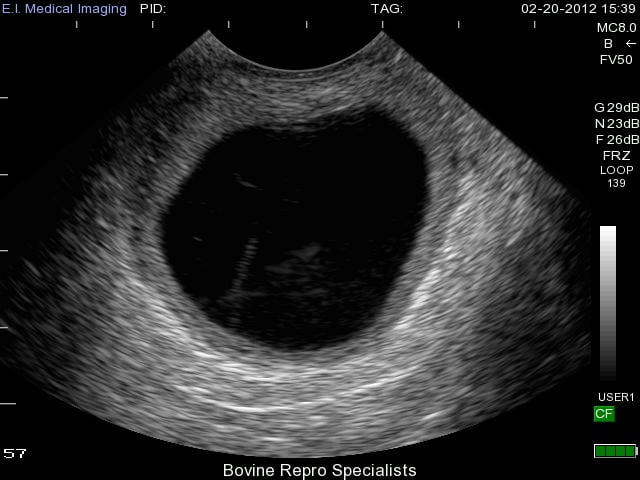

Luteal cysts are believed to develop from follicular cysts that have continued to develop into their later stages. They often progress into luteal cysts by forming a thicker wall of luteal tissue around their outer edges as shown in the image below. You can also see a very slight bit of white “cobwebs” within the lumen of the luteal cyst where the cyst appears to be attempting to further luteinize.